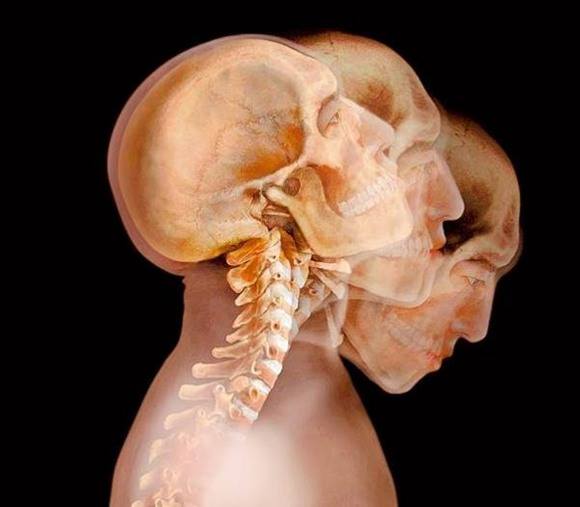

「頭」は体軸の一番上にあり、5~6キロも重さがある!

頭の位置を実際より低くイメージしている人が多いのですが、その結果せっかく使える首のカーブをほとんど使わずに固めてしまって、全身のパフォーマンスが落ちていることがあります。

実は頭とは”頭頂から耳の上まで”を指します。後屈を始める前に、あらためて自分の手で確かめてみましょう。また、”頭頂から耳の上まで”とは一体どのくらいの高さがあるか、手で測ってみましょう。(顔の半分以上あることに気づくでしょう!)また、ポーズに入る前に頭のてっぺんをトントンと手で叩くと、改めて体が頭の位置を認識するので、後屈がやりやすくなります。ぜひ試してみてくださいね。

頭と脊椎の接続部分を後屈の始点にする

後屈をするときは、頭の底、つまり首が回る一番高い位置(耳の穴くらいの高さ)から回れることを意識しながら目線を少しづつ上げて頭全体を回転していきます。後ろに一気に倒れるのではなく、繊細に少しづつ頭が持ち上がり、ゆっくり回転するのを味わいましょう。この間、「頭スイッチ!」と思って空間の中のどこに頭があるかを思い出すのも簡単であり、本能に働きかける良い方法です。